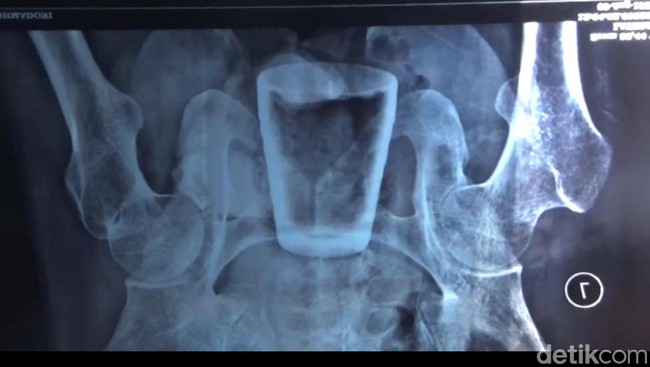

Gelas dalam perut (Yakub Mulyono/detikcom)

Gelas di dalam perut warga Jember, Jawa Timur, sudah dikeluarkan melalui operasi. Namun banyak warga yang masih mempercayai gelas di dalam perut pria tersebut gara-gara santet.